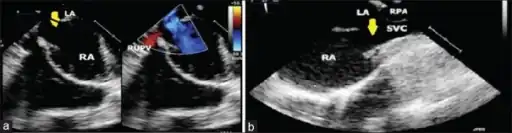

A sinus venosus atrial septal defect is a type of atrial septal defect primarily associated with the sinus venosus.

They can occur near the superior vena cava or inferior vena cava, but the former are more common.[2]

They can be associated with anomalous pulmonary venous connection.[3]